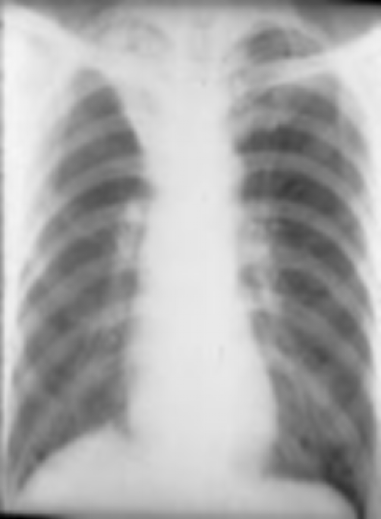

肺不张

3月龄女婴患肺炎后情况:

胸部 X 线检查所见:右下叶

肺不张的 锲形阴影(箭头)